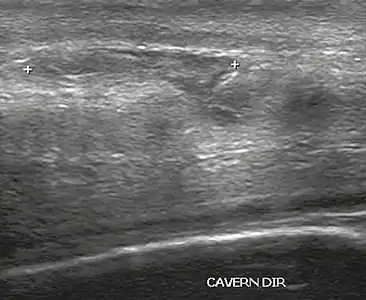

In the ultrasound examination, a lesion of the tunica albuginea presents as an interruption in (loss of continuity of) the echoic line representing it (Figure 4). Small, moderate, or broad hematomas demonstrate the extent of that discontinuity. Intracavernous hematomas, sometimes without the presence of a tunica albuginea fracture, can be observed when there is a lesion of the smooth muscle of the trabeculae surrounding the sinusoid spaces or the subtunical venular plexus.[2]

Figure 4 A: Ultrasound of the penis, right lateral view. Longitudinal section showing rupture of the tunica albuginea with an adjacent 1.92 cm hematoma (between calipers), due to trauma.[2]